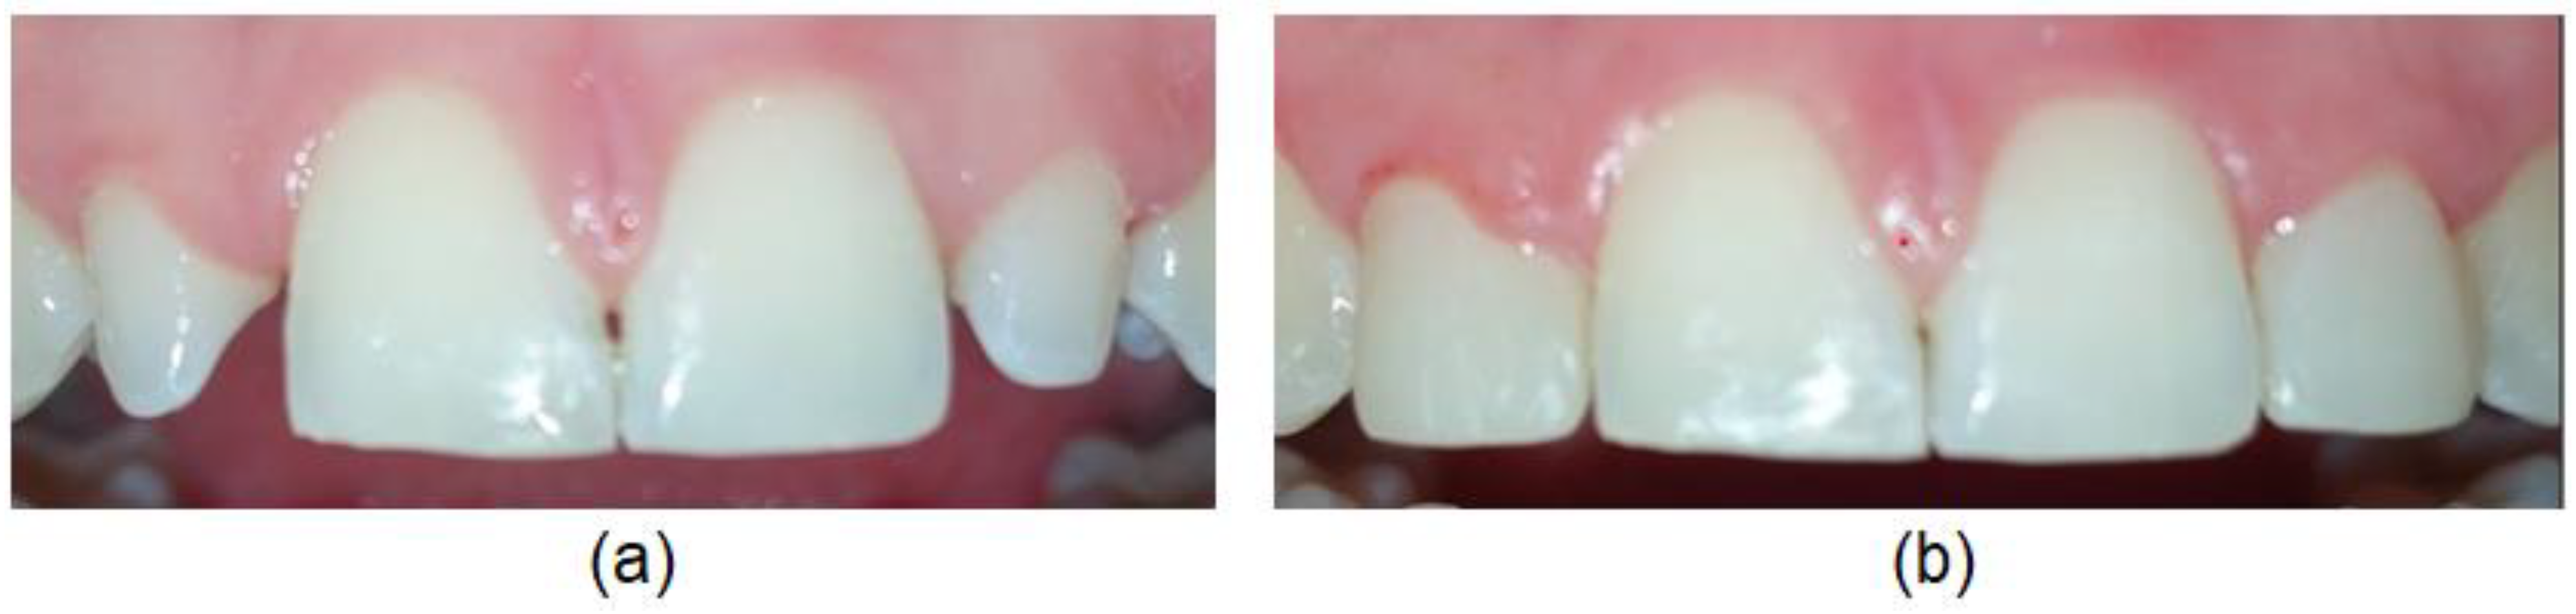

The crown morphology was evaluated and classified as trapezoidal-shaped, central incisor-shaped, canine-shaped and peg-shaped (Figure 1).

A trapezoidal-shaped permanent maxillary lateral incisor (Figure 1a) is smaller in size (shorter and narrower) than the permanent maxillary central incisor, the labial surface is more convex in form compared to the central incisor and the distal outline is more rounded with contact point at the center of the middle third.

A central incisor-shaped permanent maxillary lateral incisor (Figure 1b) is smaller in size than the central incisor but has the same general appearance.

Figure 1. Various crown morphology evaluated as: (a) trapezoidal-shaped, (b) central incisor-shaped, (c) canine-shaped and (d) peg-shaped.